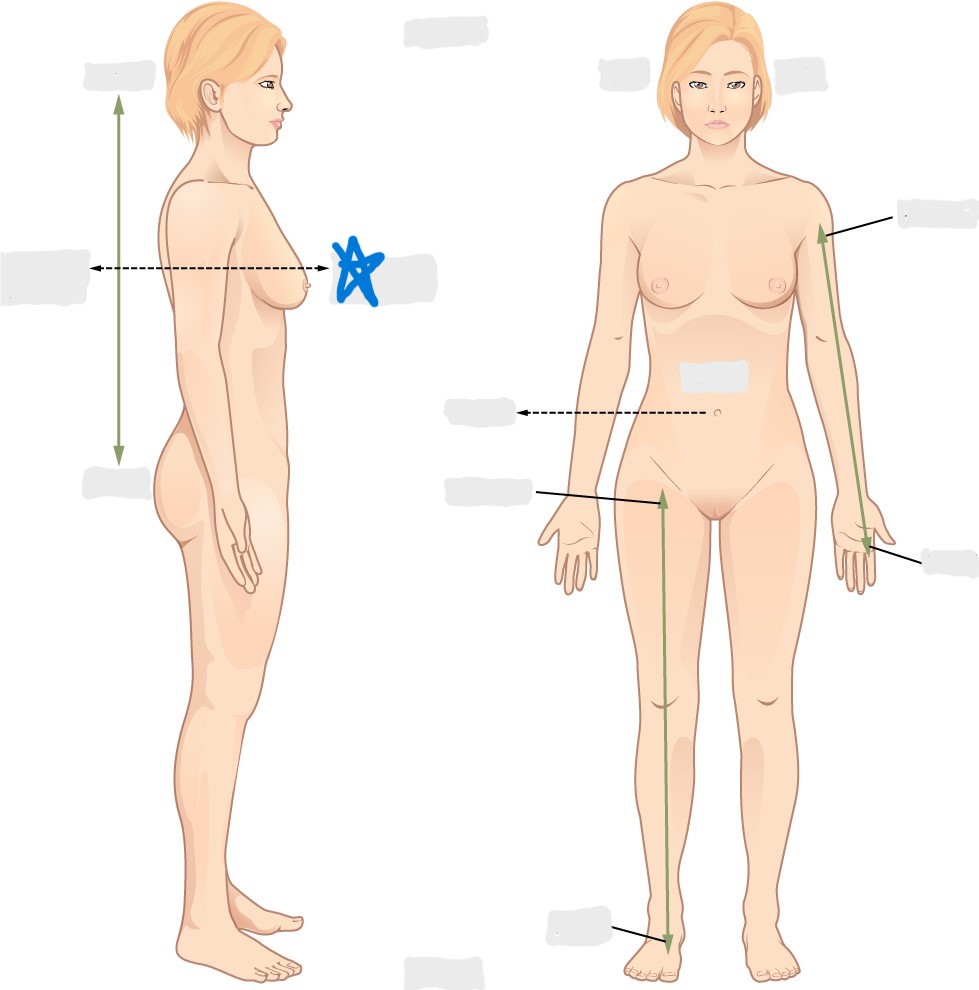

dorsal/posterior

ventral/anterior

lateral

medial

distal

proximal

superior

inferior